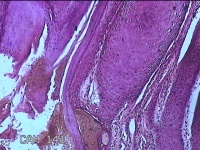

头部肿物

性别

男

年龄

21岁

临床诊断

头皮肿物

一般病史

发现头部结节10余年,无明显疼痛及不适。

标本名称

头部结节

大体所见

灰白暗红色带皮肤样结节1.5x1.3x0.3cm一个,切开结节呈实性,切面灰白粉红色,质软。